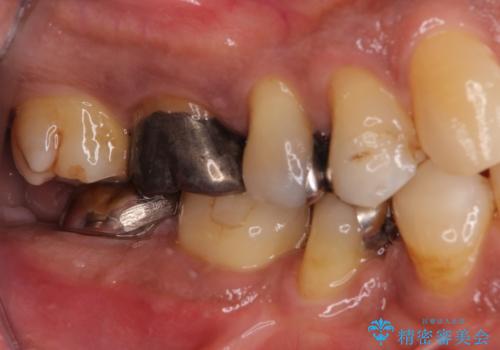

- 奥歯が痛いことを主訴に来院されました。

重度の歯周病により保存困難と診断し、抜歯後にインプラント治療を行いました。

抜歯後十分な骨の回復が認められず、単独の骨増生を行った後にインプラントを埋入しました。